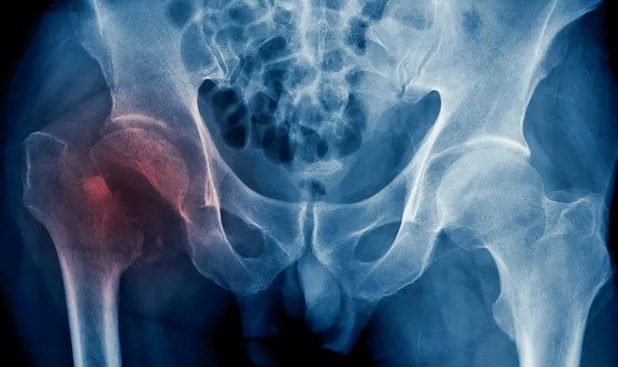

Un nuevo estudio dirigido por investigadores de la Universidad de Hong Kong ha revelado que la fractura osteoporótica de cadera, que ya es un problema peligroso y debilitante para los hombres y mujeres de edad avanzada de todo el mundo, está a punto de convertirse en un problema de salud pública mundial mucho más grave a medida que la población envejece y es más frágil, al estimar que se duplicarán en todo el planeta en 2050.

Según la investigación, el riesgo, y, por tanto, la necesidad de mejorar el estudio, la prevención y el tratamiento de la osteoporosis y las fracturas, es especialmente grande entre los hombres y los mayores de 85 años.